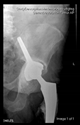

The guiding wire was inserted and controlled with fluoroscopy flashes (Figure 4). The drilling and reaming were carried out in accordance with the recommendations:

Figure 4.

The biocompatible aiming device after insertion of the guiding wire.

The direction of the cup stem was determined by the guide wire. The aiming device was needed to introduce this wire. After removing the aiming device, the next step was the drilling. Since a cannulated drill bit was used, the previously installed wire could guide the process. A self-positioning reaming tool was then used in the drilled channel. In the prepared cavity, the cup was fitted perfectly. Of the two stemmed cups available to us, the McMinn cup (Waldemar Link, Hamburg, Germany) had the simpler geometry and was therefore chosen. The stemmed cup was inserted according to the manufacturer’s recommendation. In the presence of a significant bone defect, a synthetic bone graft may be impacted for substitution.